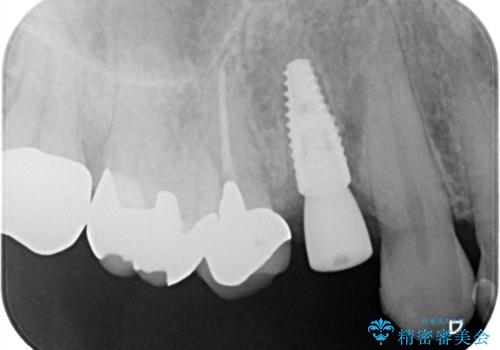

抜歯後、骨が出来るまで6ヵ月待ちその後インプラントを埋入しました。

アバットメントは患者様の歯肉に合わせて作製するカスタムアバットメントを入れ被せ物はオールセラミッククラウンで被せています。